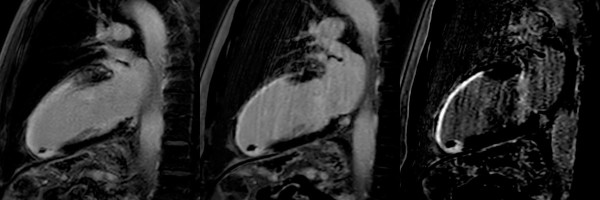

MR Cardio Narbendarstellung (PSIR Black Blood)